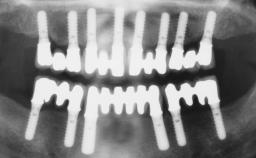

Conventional Loading of Eight Implants in the Maxilla and Final Restoration with a Full-Arch Gold-Ceramic FDP

# of Implants 8

Type of Implants One-Piece